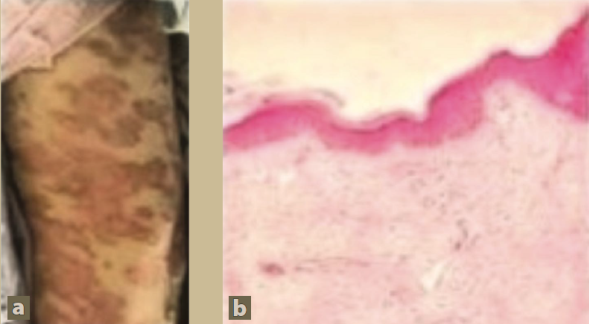

Una tomografía axial computarizada de tórax realizada el día del ingreso mostró derrame pleural bilateral e imágenes sugestivas de “vidrio despulido” en la base pulmonar derecha (figura 2a). Un ultrasonido abdominal evidenció riñones aumentados de tamaño (12 y 13 cm, respectivamente), con disminución general de la densidad y pérdida de la relación corteza-médula.

Figura 2 Tomografía axial computarizada de tórax al ingreso y después de 15 días de hospitalización

Una nueva TAC de tórax, realizada 15 días después de la inicial, mostró la aparición rápida de lesiones nodulares difusas bilaterales, algunas de ellas cavitadas (figura 2b).